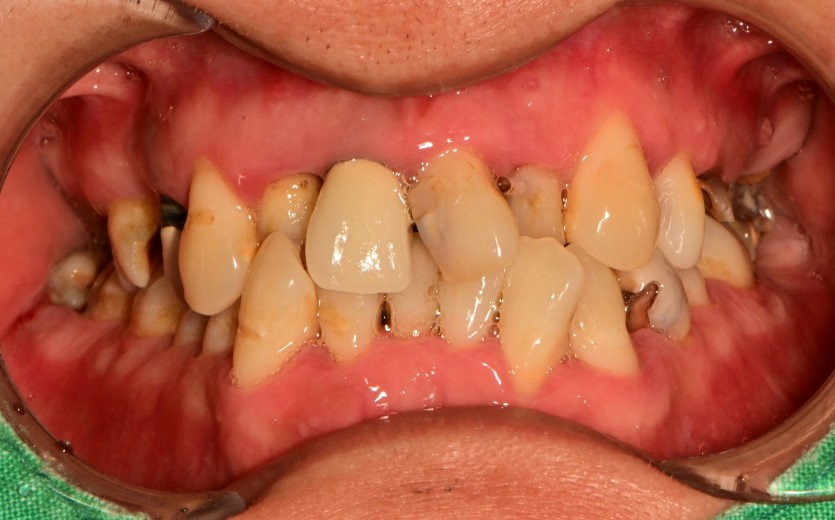

만 45세 상악 전체 임플란트 증례

상악 전체 임플란트 증례입니다.

10개의 임플란트로 완성하였습니다.